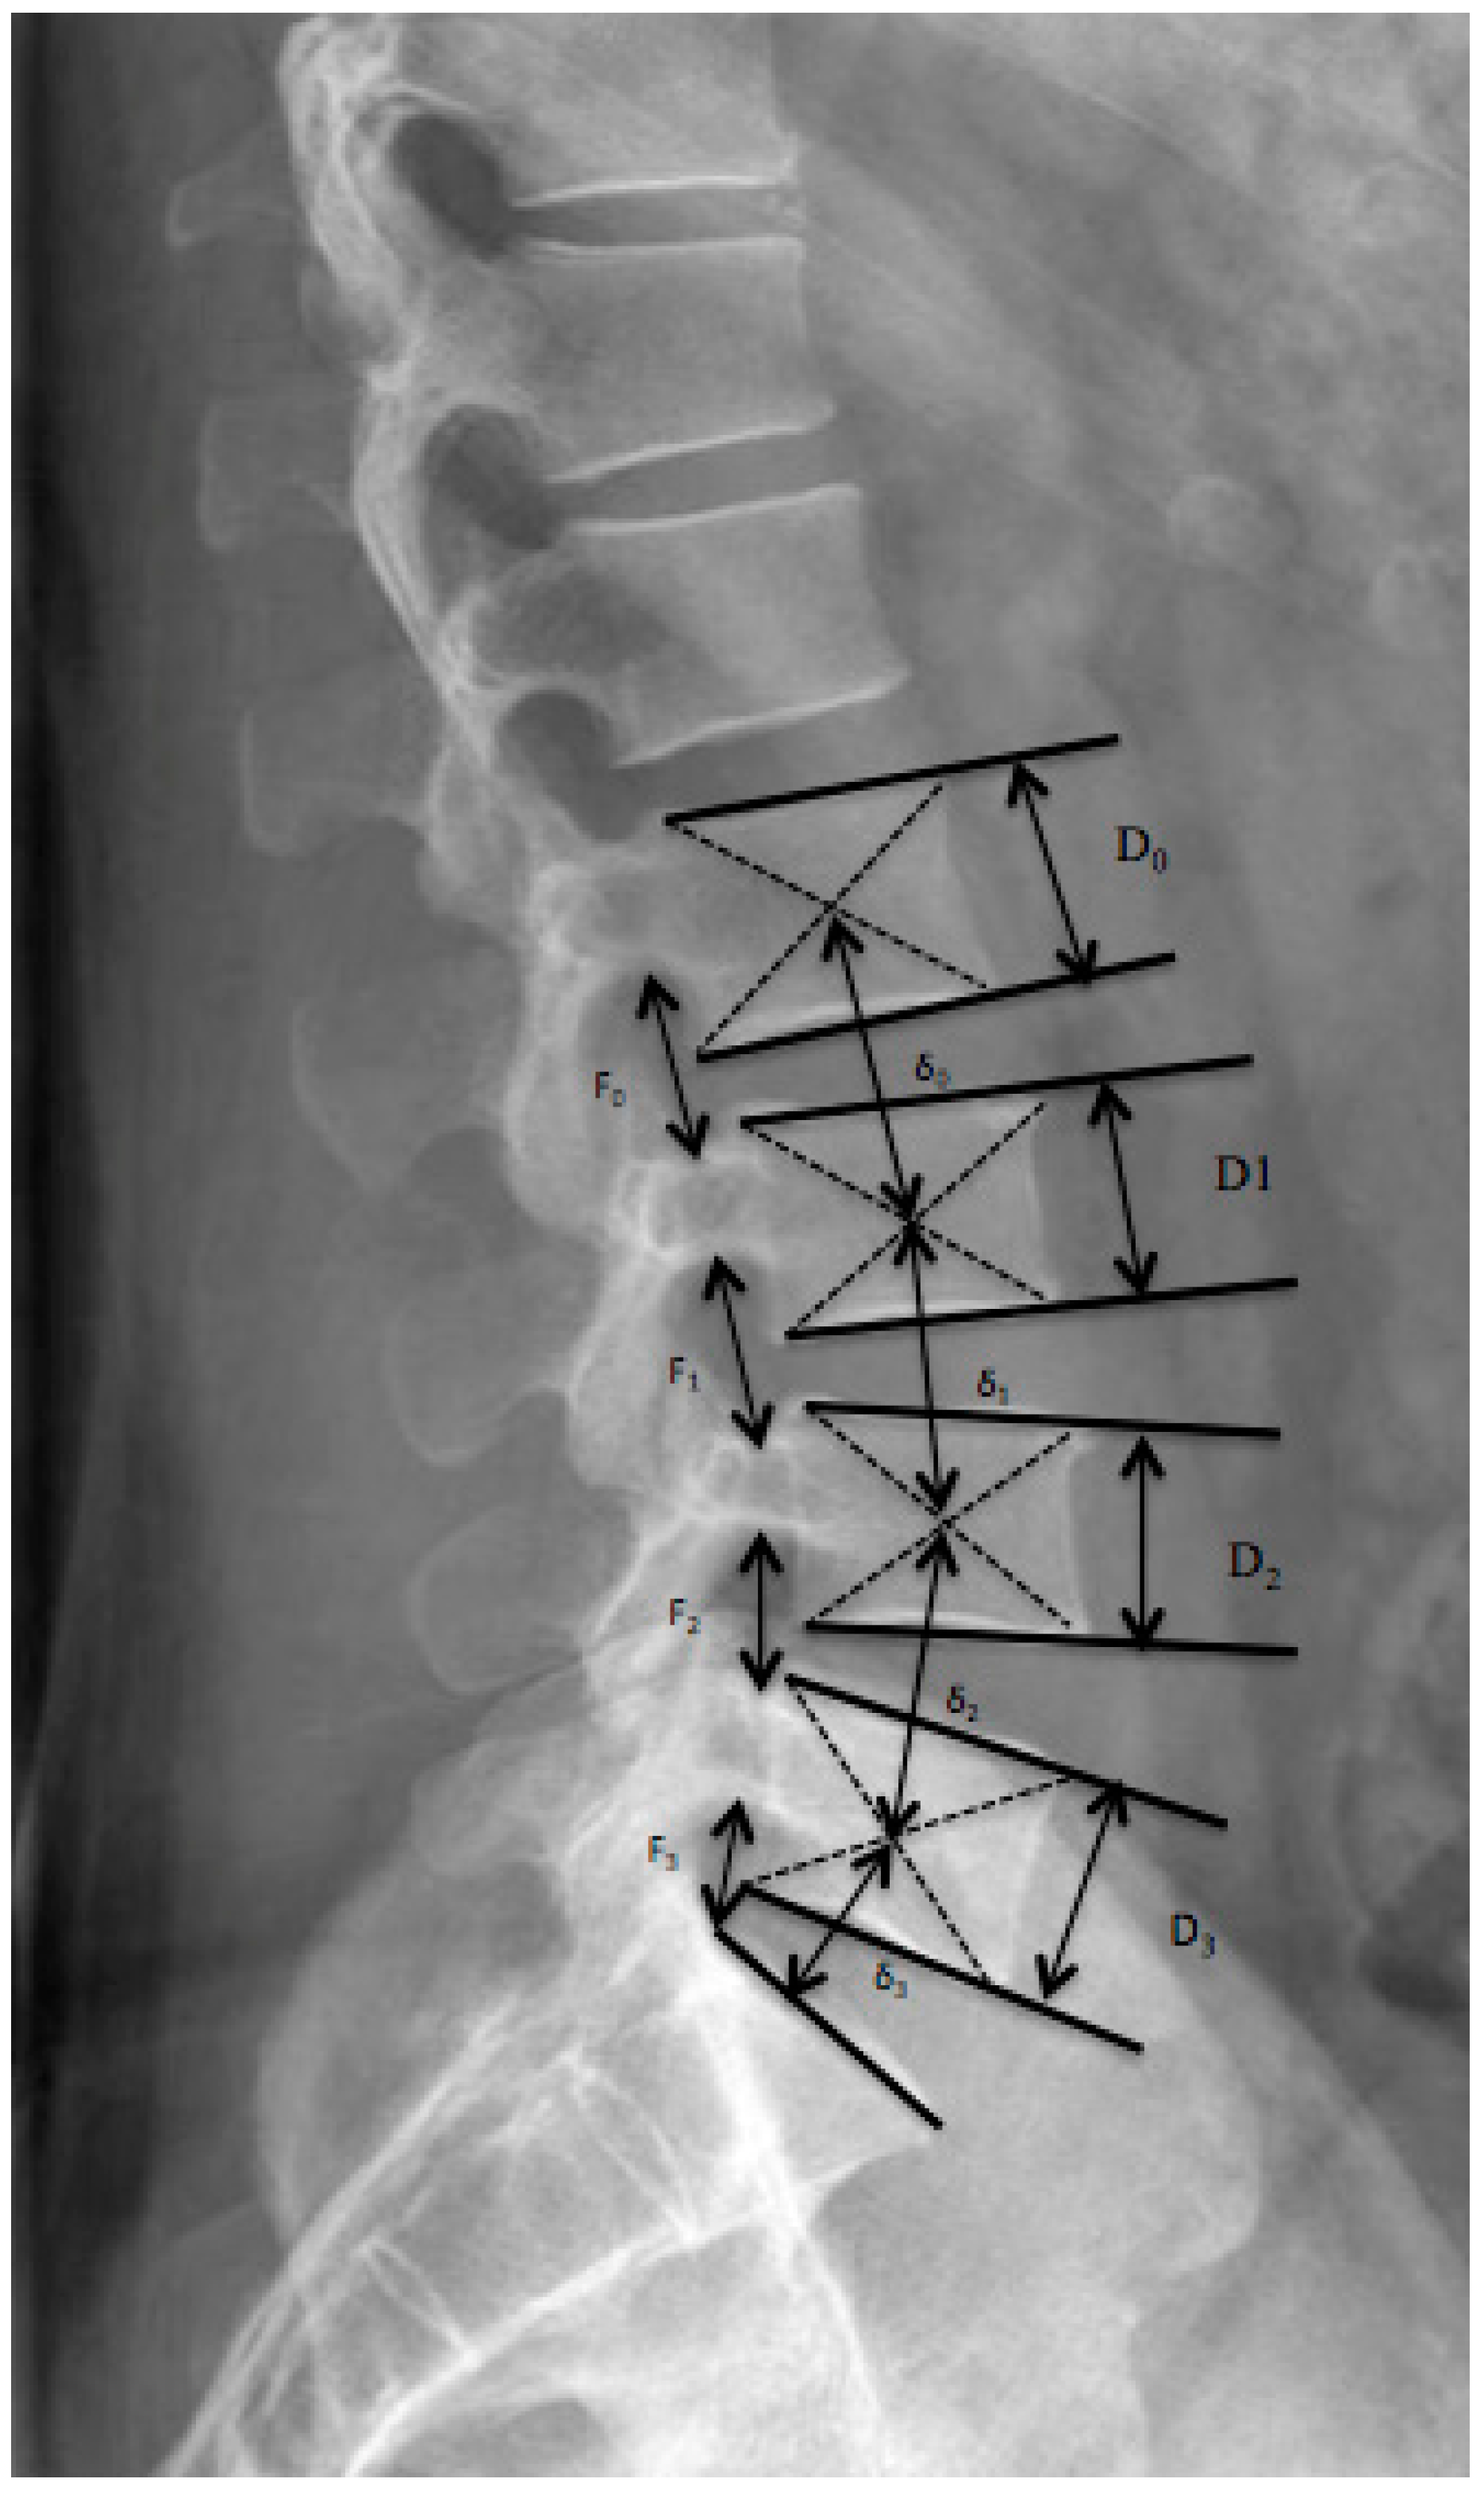

- Frobin, W.; Brinckmann, P.; Biggemann, M. Objective measurement of the height of lumbar intervertebral discs from lateral roentgen views of the spine. Z. Orthop. Ihre Grenzgeb. 1997, 135, 394–402. [Google Scholar] [CrossRef] [PubMed]